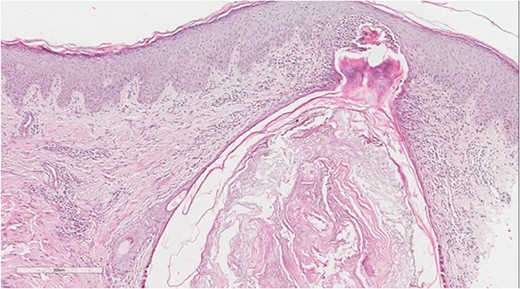

A 5 mm skin punch biopsy was also taken from the neck. Histopathology showed cystically dilated hair follicle with surrounding fibrosis and heavy inflammatory infiltrate and granulation tissue (Fig. 1), the inflammatory infiltrate is composed of lymphocytes, plasma cells, neutrophils and histiocytes (Fig. 2). The overall morphologic picture was suggestive of follicular occlusion syndrome (Fig. 3). A diagnosis of HS was made, and the patient was started on rifampin 600 mg OD and clindamycin 300 mg BID. A lipid panel was ordered as well and showed a triglyceride level of 1.99 mmol/L (0.7–1.7 mmol/L).

Dilated hair follicle with perifollicular inflammation and adjacent foreign body giant cell reaction secondary to ruptured dilated hair follicle in a background of dermal fibrosis.